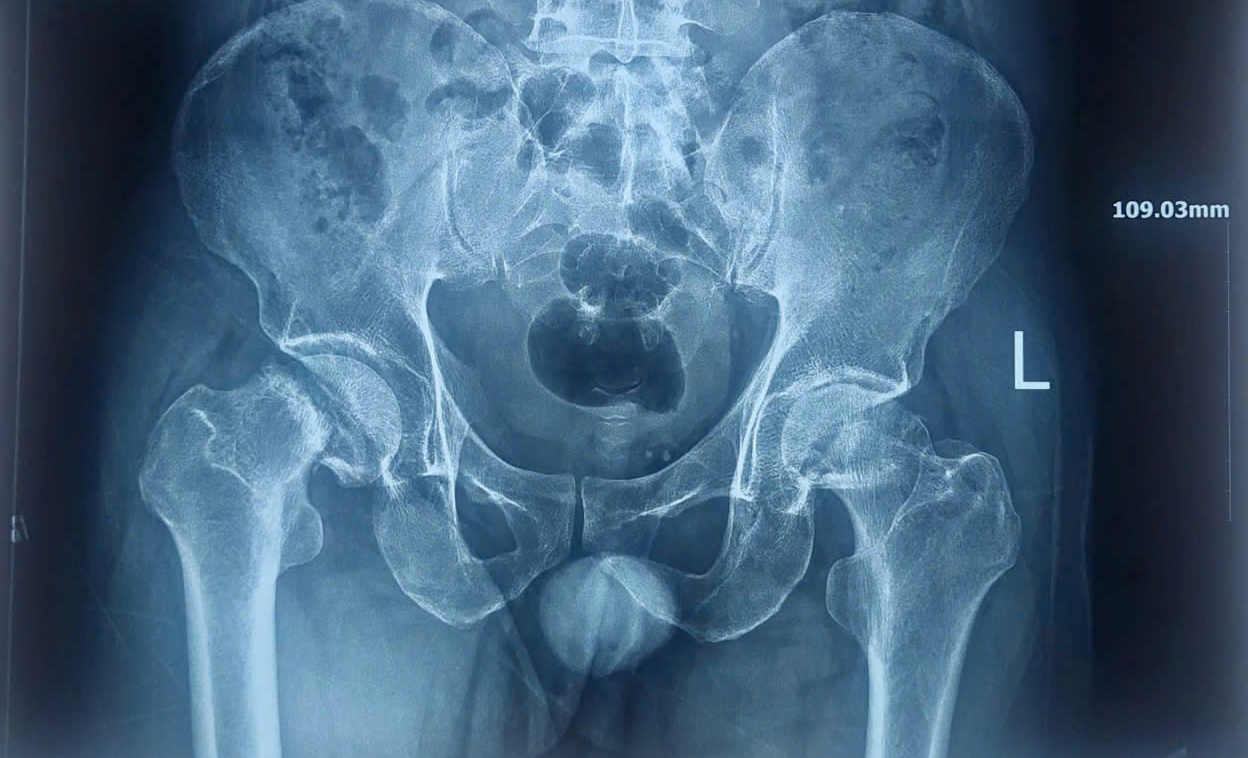

Hình ảnh X-quang trước phẫu thuật cho thấy bệnh nhân bị hoại tử nặng chỏm xương đùi 2 bên

Qua thăm khám, xét nghiệm, chẩn đoán hình ảnh, các bác sĩ xác định bệnh nhân bị hoại tử chỏm xương đùi 2 bên. Nguyên nhân là do giảm hoặc mất nguồn máu nuôi chỏm xương đùi, dẫn đến hoại tử xương.